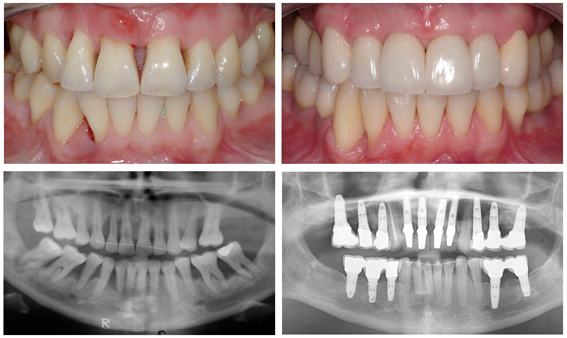

- Smile design for full-mouth makeovers